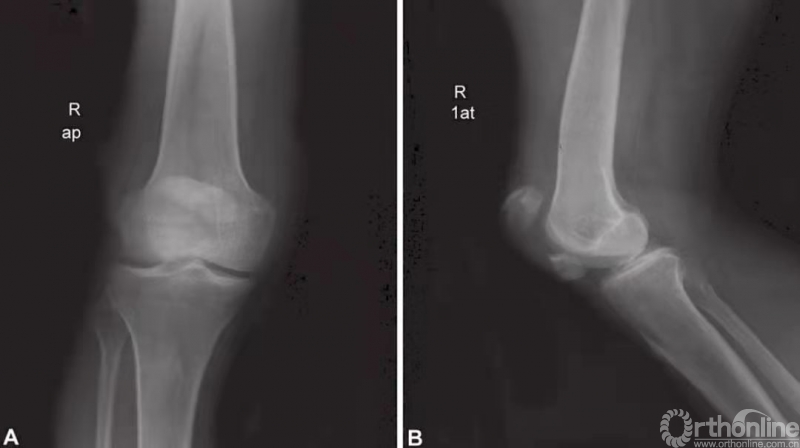

检查针对髌骨骨折的患者,标准的膝关节前后位片、侧位片(图1A和B)是必须的,有时还需加拍特殊体位的平片(轴位片),以便对患者的病情进行可靠的评估以及术前规划。在前后位片上,因股骨髁的重叠影,很难对髌骨骨折进行完善的评估。侧位片可对髌骨的形态进行较好的呈现,可评估其骨折线、骨折移位程度以及髌骨的位置。二分髌骨易与髌骨骨折混淆,然而,该疾病的髌骨分线一般位于髌骨的上外侧角,而且常呈环型,边缘圆润,硬化。髌骨轴位片一般用于髌骨纵行骨折的诊断,以及对髌-股关节稳定性的评估。其他检查,比如关节镜、CT、MRI,以及标准层析成像技术,很少运用于髌骨骨折的诊断及评估。

图1 A和B髌骨横断型骨折——术前前后位片以及侧位片